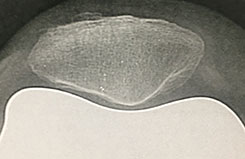

Radio post-opératoire de la rotule après prothèse Origin